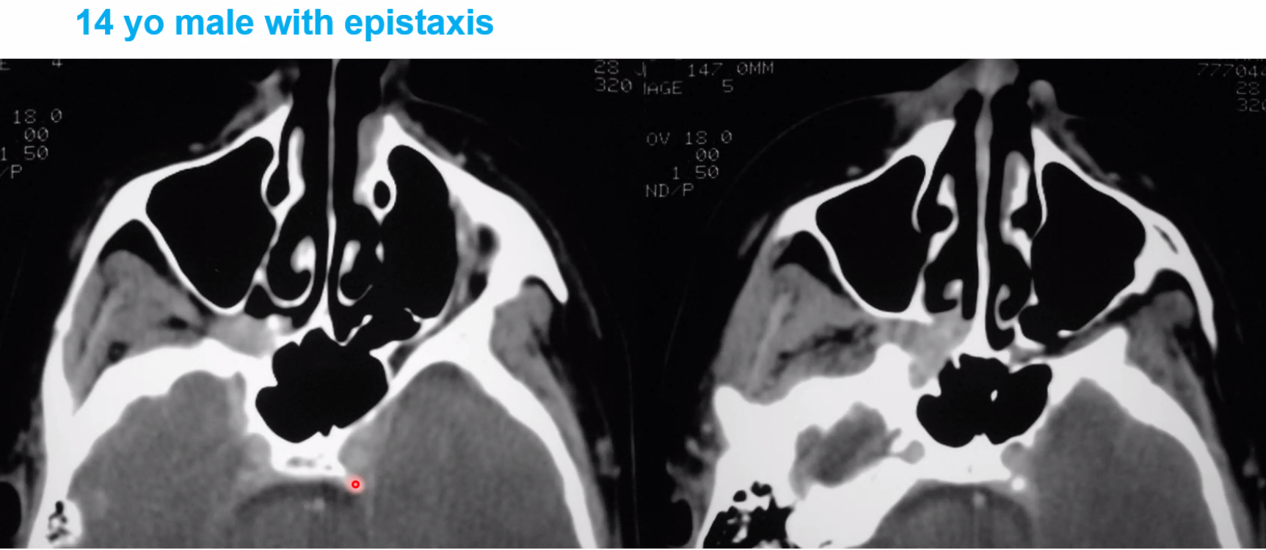

left AICA aneurysm

key is the CTA of the head –> think they are showing an aneurysm